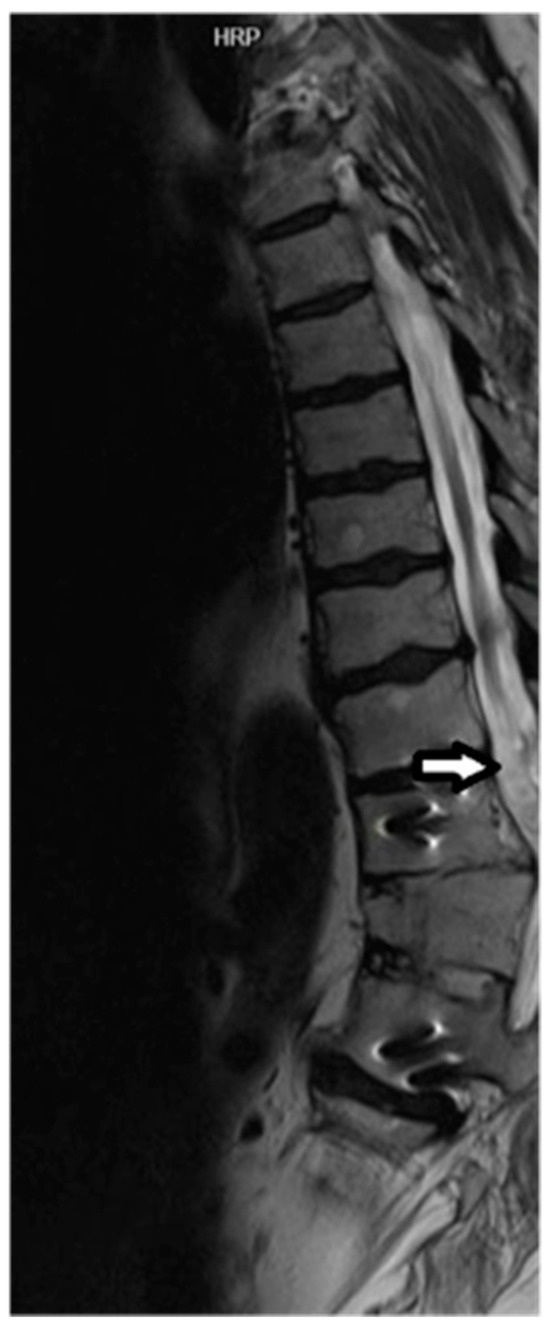

All four subjects were able to complete baseline and one-year MRI studies. All four subjects attended their scheduled appointments. Representative MRI images are presented in Figure 1 and Figure 2.

Figure 1.

Sagittal T2 image demonstrating cord hyperintensity and volume loss proximal to the level of the TSCI (arrow). Cord T2 hyperintensity at the level of T11 vertebra corresponds to a neurological deficit found during the clinical exam. Metallic artifacts within the T11 and L1 vertebral bodies related to orthopaedic hardware from prior posterior decompression and fusion was observed. There is also a chronic anterior compression fracture of T12 noted.

Sagittal T12 post processing MRI diffusion tractography imaging (DTI) demonstrates tapering of tract fibers in the lower thoracic cord proximal to the level of injury, corresponding to the volume loss, in keeping with Wallerian degeneration.